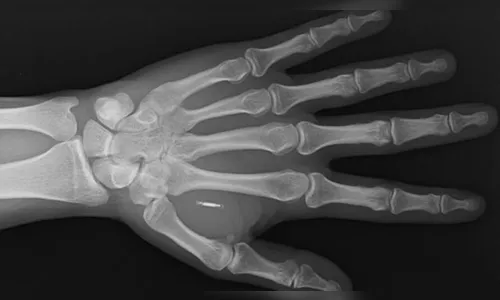

Contudo, a modificação corporal dentro dessa ciência envolve também implantação de microchips. Esses dispositivos têm circuitos eletrônicos e uma peça para se comunicar com outros aparelhos por ondas de rádio.

A professora de biotecnologia da Universidade de São Paulo (USP), Fernanda Matias, explica que tal dispositivo é usado para armazenar e transmitir informações. Eles podem funcionar através de ondas de rádio, sensores integrados ou sinais elétricos. O chip pode ser implantado no corpo em poucos minutos e o processo geralmente é tão simples quanto pôr um piercing.

Além disso, a estrutura do microchip é composta por uma espécie de vidro e, por ser biocompatível, não causa reação alérgica.

O implante de pequenas pastilhas de ímãs na ponta dos dedos funciona para que pessoas tenham uma sensibilidade extra: sentir campos magnéticos ao seu redor.